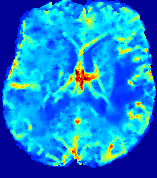

LesionRefer to captionRefer to captionRefer to captionRefer to captionRefer to captionRefer to caption𝐕rgbsubscript𝐕𝑟𝑔𝑏{\bf{V}}_{rgb}Refer to captionRefer to captionRefer to captionRefer to captionRefer to captionRefer to caption𝐕2subscriptnorm𝐕2{\|\bf{V}}\|_{2}Refer to captionRefer to captionRefer to captionRefer to captionRefer to captionRefer to captionRefer to caption3.53.53.52.82.82.82.12.12.11.41.41.40.70.70.70.00.00.0(mm/s)𝑚𝑚𝑠(mm/s)D𝐷DRefer to captionRefer to captionRefer to captionRefer to captionRefer to captionRefer to captionRefer to caption0.0200.0200.0200.0160.0160.0160.0120.0120.0120.0080.0080.0080.0040.0040.0040.0000.0000.000(mm2/s)𝑚superscript𝑚2𝑠(mm^{2}/s)Slice #1Slice #2Slice #3Slice #4Slice #5Slice #6

Figure 3: PIANO feature maps for one stroke patient, where the lesion is located in the left hemisphere. Top row: segmented stroke lesion region (white) on different slices, obtained from ISLES 2017. The corresponding slices for the PIANO feature maps are shown in the following rows.

For a better insight into an estimated velocity field 𝐕𝐕{\bf{V}} and diffusion field 𝐃𝐃{\bf{D}}, we compute the following maps: (1) 𝐕rgbsubscript𝐕𝑟𝑔𝑏{\bf{V}}_{rgb}: Color-coded orientation map of 𝐕=(Vx,Vy,Vz)T𝐕superscriptsuperscript𝑉𝑥superscript𝑉𝑦superscript𝑉𝑧𝑇{\bf{V}}=(V^{x},V^{y},V^{z})^{T}, obtained by normalizing 𝐕𝐕{\bf{V}} to unit length and mapping its 3 components to red, green, blue respectively; (2) 𝐕2subscriptnorm𝐕2\|{\bf{V}}\|_{2}: 222 norm of 𝐕𝐕{\bf{V}}; (3) D𝐷D: scalar field in Eq. 5.

Fig. 3 and Fig. 4 show the PIANO feature maps estimated from two ISLES 2017 patients: all are highly consistent with the lesion in both cases. Details of the blood flow trajectories are revealed in 𝐕rgbsubscript𝐕𝑟𝑔𝑏{\bf{V}}_{rgb} by the ridged patterns and the sharp changes of colors in the unaffected (right) hemisphere, while the flat patterns appearing within the lesion provide little directional information about the velocity and indicate low velocity magnitudes. Velocity magnitudes are more directly visualized via 𝐕2subscriptnorm𝐕2\|{\bf{V}}\|_{2}, from which one can easily locate the lesion where 𝐕2subscriptnorm𝐕2\|{\bf{V}}\|_{2} is low. D𝐷D also indicates lower diffusion values in the lesion, though with less contrast potentially due to the fact that it captures the accumulated effect of CA diffusion at the voxel-level.